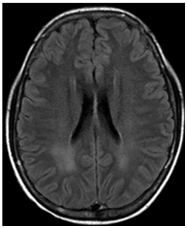

Two days after aminophylline was started, there was improvement of areas with high DWI signal. Four days later, the patient recovered movements on the face and upper limbs. In the two- week follow-up, demonstrated areas of high signal in T2 in correspondence previous areas of change of signal in DWI. (Figures 6‒8).

Figure 7 (FLAIR) now it is possible to identify correspondently high signal FLAIR images.

Figure 8 (FLAIR) now it is possible to identify correspondently high signal FLAIR images.